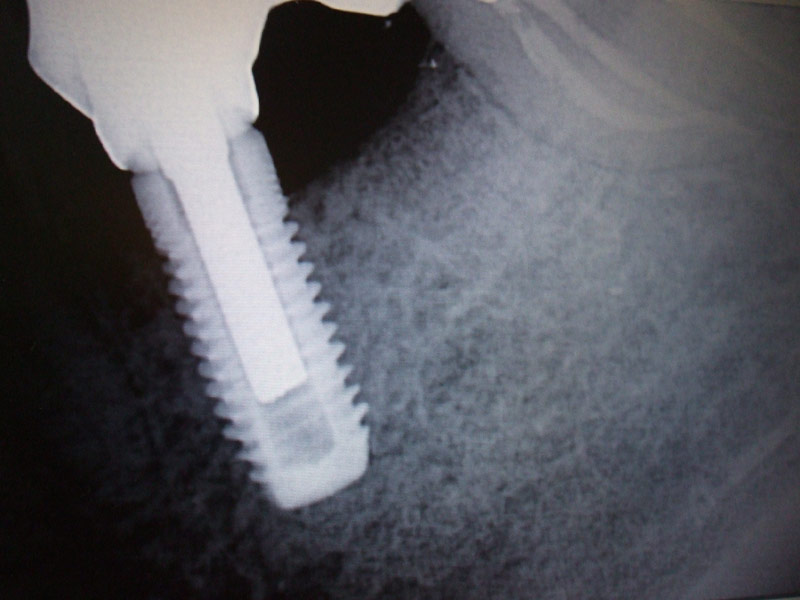

Ragazza di circa trenta anni con perdita del primo molare di destra inferiore(36) per carie destruente. E' stato inserito un impianto di diametro 4mm per 12mm di lunghezza utilizzando poi una vite di chiusura più alta transmucosa per evitare un secondo intervento chirurgico di scopertura dell'impianto su una gengiva già guarita.

Nel caso in questione si descrive un mono impianto con vite di chiusura trans-mucosa senza necessità di secondo intervento chirurgico di scopertura dell'impianto.